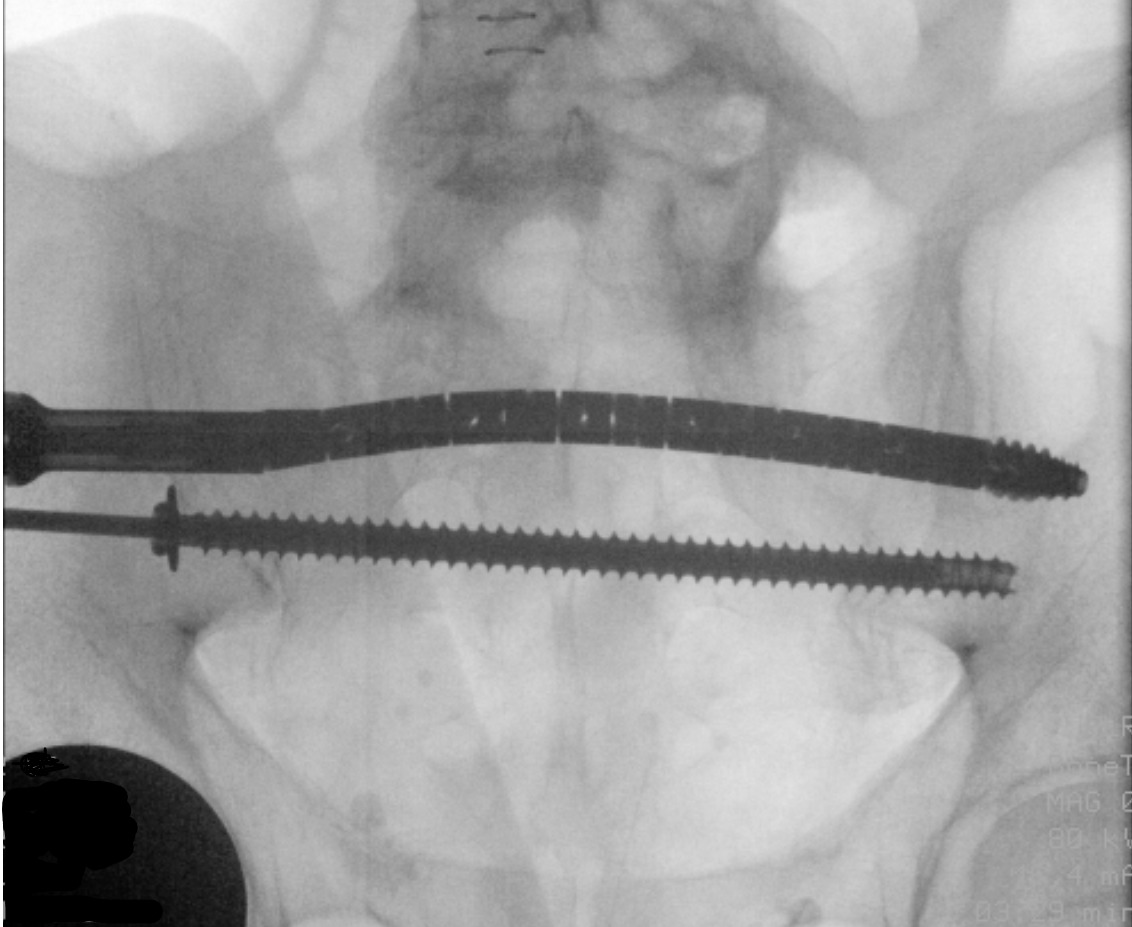

The CurvaFix implant is attached to the inserter and torque handle, then advanced over the driving guidewire using the torque handle. Once the implant is seated, the handle is turned until the inserter fins are parallel to the ground. The guidewire is removed, then the locking mechanism is activated. The inserter and torque handle are removed (Figure 3).